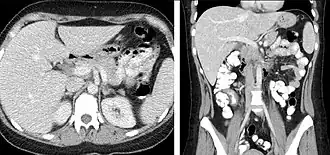

Portal venous phase

The most common technique is to perform portal venous phase imaging in the abdomen and pelvis (approximately 60–90 seconds after contrast administration, figure 2). This results in near optimal contrast opacification of the majority of the solid abdominal organs and it is used for a wide variety of indications: nonspecific abdominal pain; hernia; infection; masses (with a few exceptions such as hypervascular, renal, and some hepatic tumors); and in most follow-up examinations. As a general rule, this single phase is adequate unless there is a specific clinical indication that has been shown to benefit from other phases.

-

FIGURE 2. Contrast enhanced CT demonstrating parenchymal enhancement of the intra-abdominal organs in the portal venous phase (axial left, coronal reformat right).